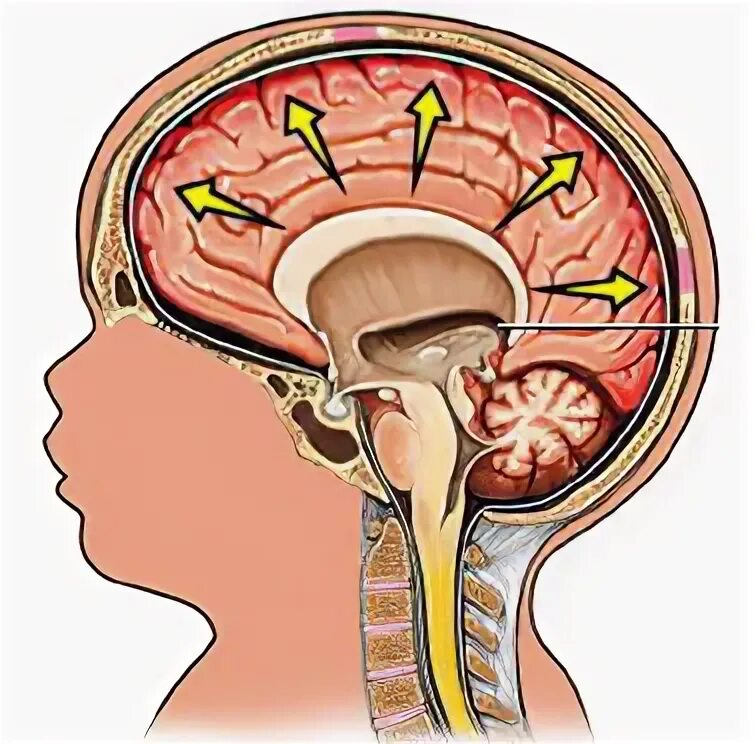

Давление изнутри головы